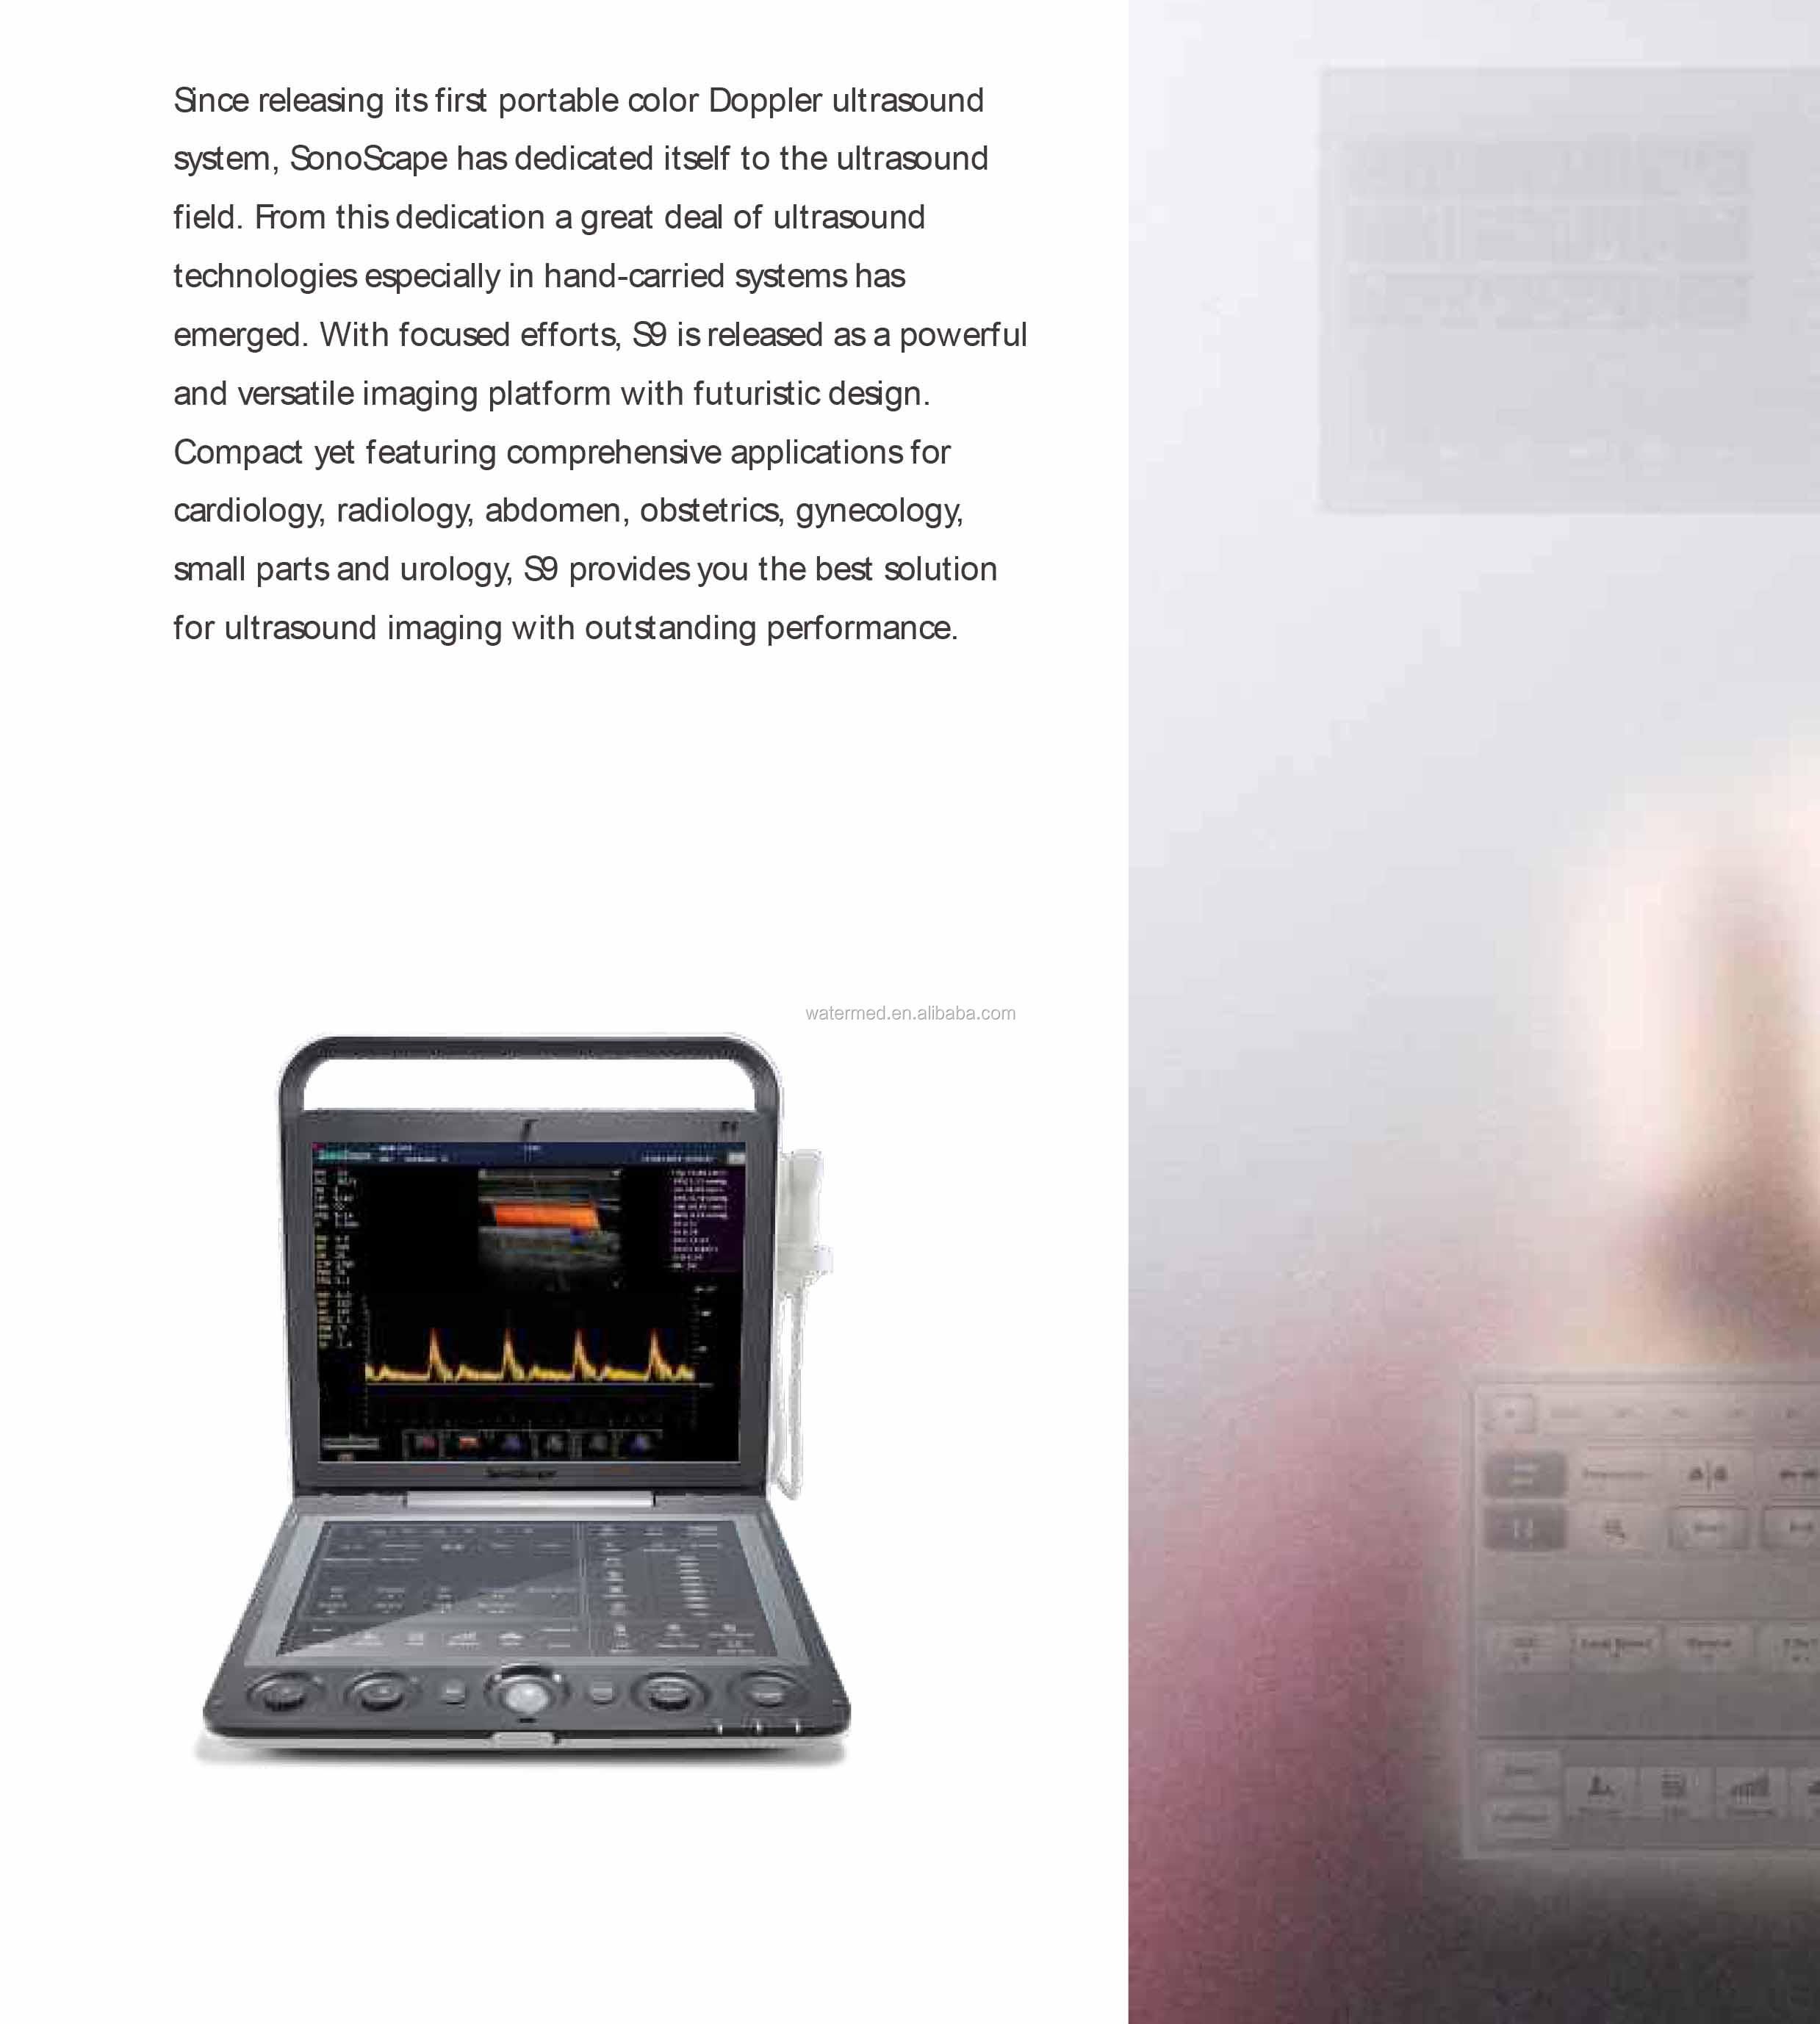

Portable 3D 4D Color Doppler USG&Sonoscape S9

SonoScape has been in the field of ultrasound since releasing the first portable color Doppler ultrasound system. From this dedication, a large number of ultrasound technologies have emerged, especially in hand-held systems. Out of this dedication, the S9 was released as a powerful and versatile imaging platform with a futuristic design. Small in size and wide in application, the S9 is suitable for Cardiology, Radiology, Abdominal, Obstetrics, Small Parts and Urology, providing the best solution for ultrasound imaging with outstanding performance.